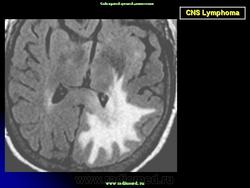

Локализируется в основном в больших полушариях. Некоторые больные могут иметь лимфому в других частях тела. В головном мозгу, не редко, могут иметь место множественные локализации. Диагноз подозревается на основе изображений КТ и МРТ.

Диагноз подозревается на основе изображений КТ и МРТ.

Церебральная лимфома